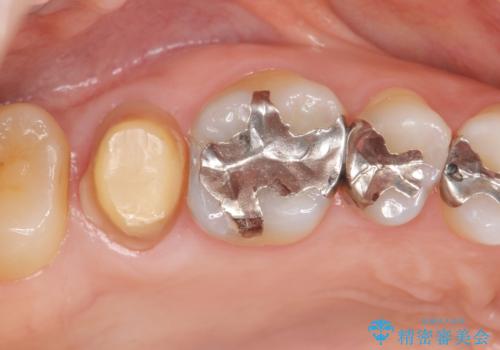

- 奥歯に違和感があることを主訴に来院された患者様です。

精査したところ、右上の奥歯(右上7)はう蝕が深く骨吸収も進行しており保存不可能な状態でした。

金属アレルギーの疑いがあり、インプラントも避けたいとの患者様のご希望により、親知らずを移植することにしました。

移植がうまくいかない可能性を考慮し、ブリッジもできるよう隣の親知らず(右上8)は残し、反対側の親知らず(左上8)を移植しました。